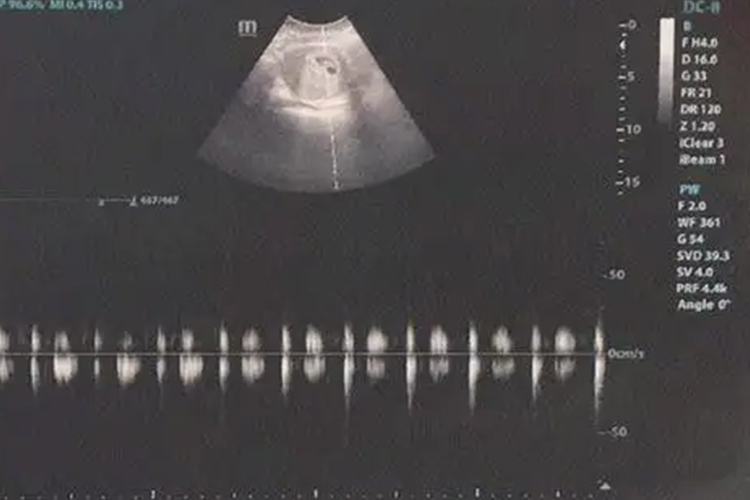

怀孕40天尚未形成一完整的胚胎,此时一般可见妊娠囊形态。怀孕40天,超声检查宫腔内见到圆形或椭圆形妊娠囊,它是由绒毛膜形成的环形结构,环内为无回声暗区,外围为强回声环,强回声环外是低回声环。

因此,双环征是早期妊娠囊在超声下的重要特征。怀孕40天时,部分孕妇超声下可见到胚芽和原始心管搏动。